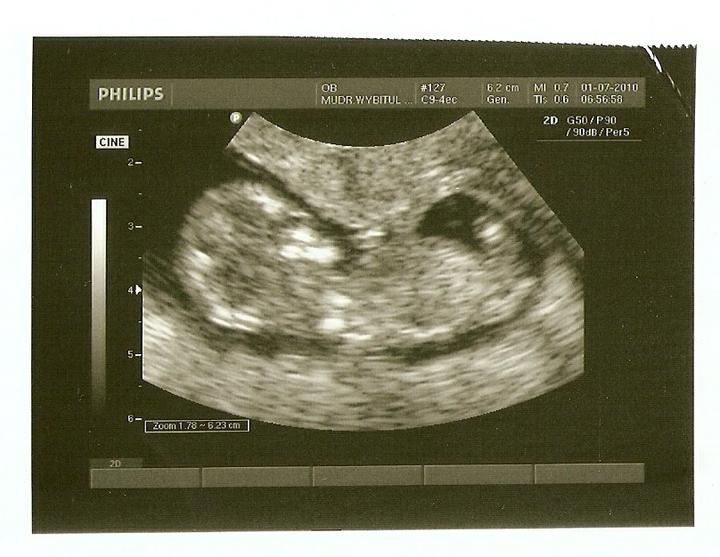

Těhotenský test v IVF

Domácí těhotenský test se obvykle doporučuje udělat nejméně 10 dnů po poslední dávce Pregnylu. Záleží tedy na tom, zda při punkci vaječníků byl získán nižší počet oocytů, a proto byly aplikovány ještě 1 až 3 menší dávky Pregnylu nebo zda byl získán větší počet oocytů a Pregnyl se aplikoval pouze před punkcí.

- možnost zachycení biochemického těhotenství, které neprosperuje. Je poměrně běžné, u přirozeného cyklu se děje také často - žena ani neví, že je těhotná, jen se jí případně mírně opozdí menstruace. Tento termín označuje situaci, kdy dojde k uhnízdění embrya, které však bylo slabé nebo nekvalitní a po čase se rozpadá. Vzhledem k tomu, že po IVF má většina žen tendenci testovat příliš brzy a velmi citlivým testem, takovéto těhotenství se může zachytit. Je to ale ještě také příliš brzo, aby těhotenství bylo možné potvrdit na ultrazvuku. Označuje se tedy jako "biochemické", protože je zjištěno pouze testem z moči, případně z krve (narozdíl od zamlklého těhotenství, které bylo již prokázáno nálezem na ultrazvuku). U testu z krve se obvykle vyskytují nízké hodnoty, které při opakovém provedení klesají.